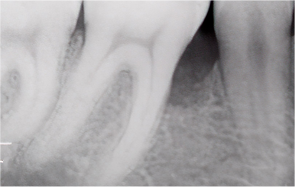

When the gingiva (periodontal tissue) has receded or the alveolar bone has been resorbed, scaling alone has its limits. Gum regeneration therapy regenerates damaged tissue to preserve natural teeth and restore function.

Even when severe periodontal disease has caused gingival recession and alveolar bone resorption, teeth can often be preserved through gum regeneration therapy using Emdogain. This procedure regenerates damaged alveolar bone and surrounding periodontal tissue. By applying Emdogain — a specialized gel that stimulates periodontal tissue regeneration — the supporting structures of the tooth are rebuilt, allowing function and health to be restored without extraction.

Emdogain Clinical Evidence

Across more than 40 clinical studies involving over 1,500 intrabony defects, Emdogain has been proven effective in stimulating new periodontal attachment formation. To date, no adverse effects have been reported in professional clinical use or clinical research.